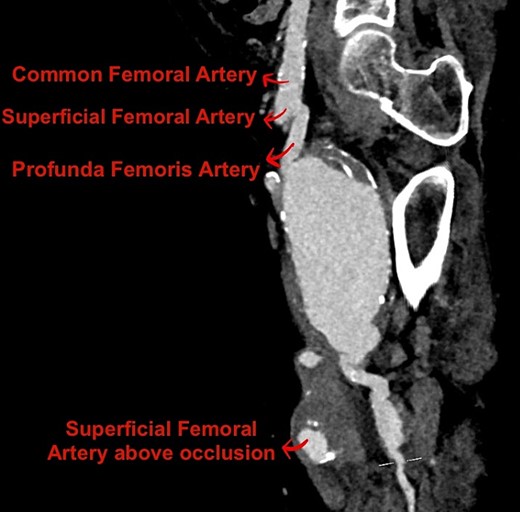

CT angiogram of the lower limbs showed her previously known aneurysms, as well as a 65 mm aneurysm arising from the proximal left PFA (Fig. 1), with an associated 36 mm pseudoaneurysm likely representing a contained rupture.

Reconstructed sagittal view of the CT angiogram lower limb showing the PFAA.